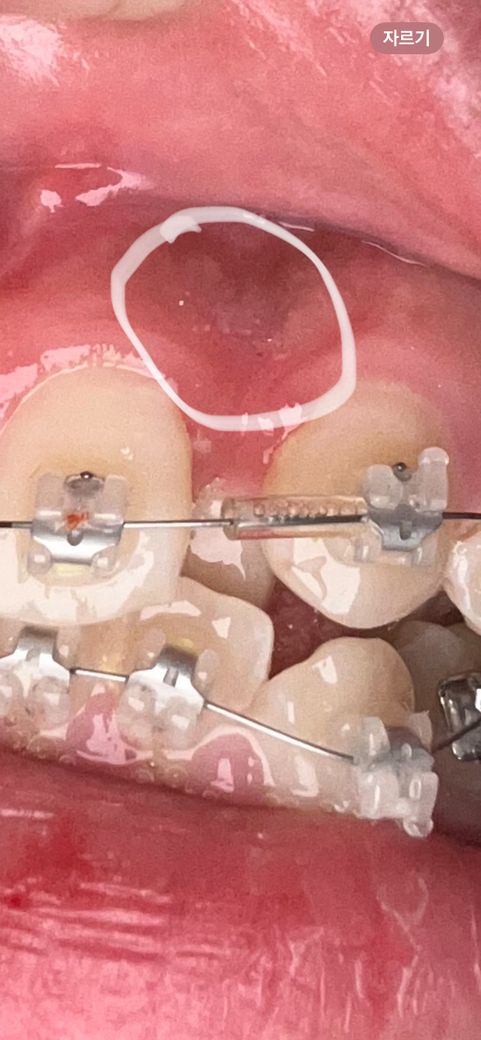

교정한지 일주일이 넘었는데 앞니가 밑에 있는이랑 닿을때마다 잇몸? 신경?이 찌릿찌릿하고 아파요 원래 이런건가요? 그리고 잇몸이 뭐라해야하지 사진처럼 막 하얀 점 같은것들이 생겻는데 저건 뭔가요?

• 1번 째 사진

잇몸에 생기는 것과 불편한 느낌은 일시적인 증상일 가능성이 큽니다. 교정 중에는 치아에 통증을 느끼기도 하고 다양한 잇몸 부작용이 나타납니다.